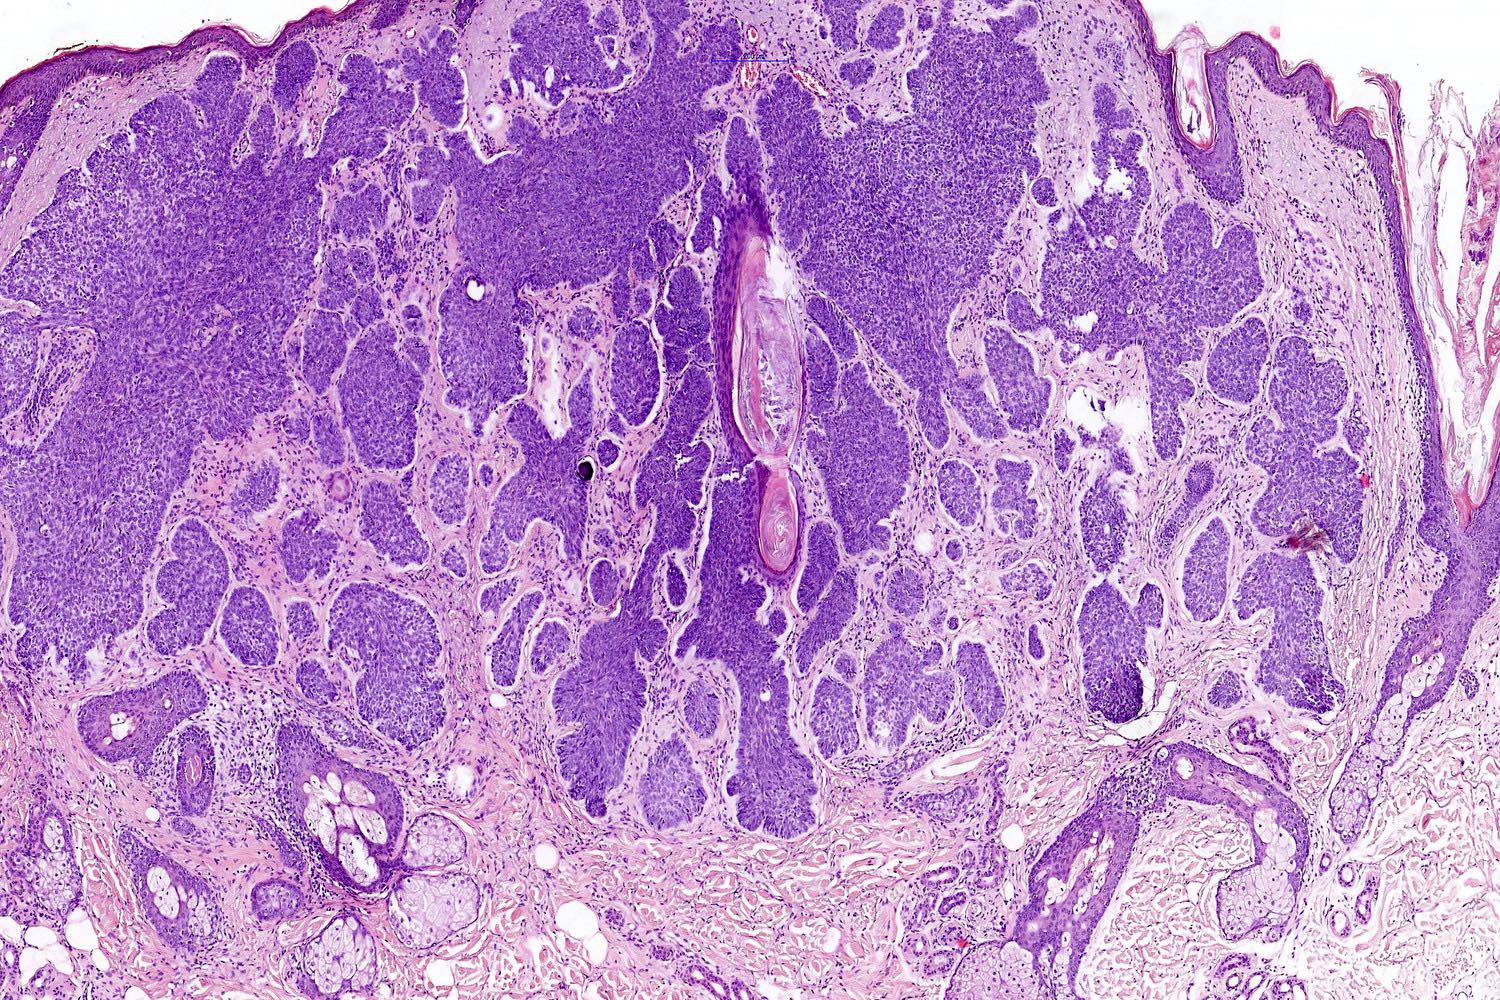

Common variants (Calonje: McKee's Pathology of the Skin, 5th Edition, 2019)

- Nodular and nodulocystic BCC

- Relatively circumscribed mass

- Epidermal or follicular attachment variably present

- Large basaloid lobules with peripheral nuclear palisade

- Lobules may be solid or show central cyst formation due to excessive mucin production

- Fibromyxoid stroma

- Cleft formation between tumor lobules and stroma

- Superficial BCC

- Isolated basaloid lobules projecting from the lower margin of the epidermis

Microscopic (histologic) images

Contributed by Antonina Kalmykova, M.D., Phillip H. McKee, M.D., Sate Hamza, M.D., Eduardo Calonje, M.D.,

Wayne Grayson, M.B.Ch.B., Ph.D., James Sampson, M.B.B.S., M.Sc. and Assia Bassarova, M.D., Ph.D.